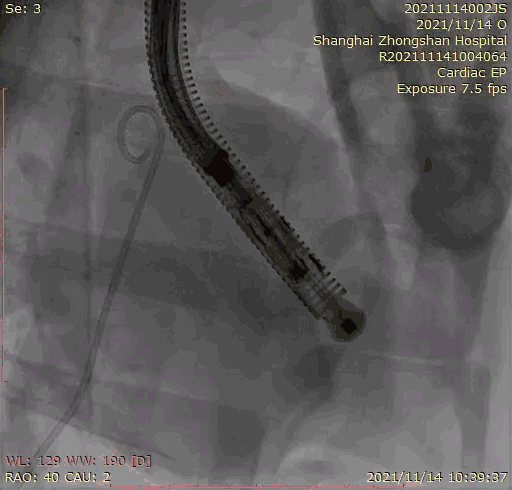

葛均波院士團(tuán)隊(duì)成功應(yīng)用Lux-Valve Plus完成經(jīng)血管介入三尖瓣置換臨床前研究!

2021年11月14日星期日,復(fù)旦大學(xué)附屬中山醫(yī)院(以下簡稱中山醫(yī)院)葛均波院士團(tuán)隊(duì)成功應(yīng)用經(jīng)血管介入三尖瓣置換產(chǎn)品Lux-Valve Plus完成臨床前研究,并獲得圓滿成功!此次研究的成功預(yù)示經(jīng)血管三尖瓣產(chǎn)品Lux-Valve Plus已完成臨床前準(zhǔn)備,即將開啟后期的正式臨床研究!

上海中山醫(yī)院葛均波院士、錢菊英院長、周達(dá)新教授、潘文志教授、潘翠珍教授、李偉教授共同完成此次臨床前研究。術(shù)后葛均波院士對Lux-Valve Plus的器械操作性能給予了高度評價,DSA和超聲影像也顯示出在本次研究中Lux-Valve Plus的安全性和有效性俱佳。

本次臨床前研究經(jīng)右側(cè)頸靜脈置入LuX-Valve Plus輸送系統(tǒng)可調(diào)彎鞘管,在DSA及超聲引導(dǎo)下將人工三尖瓣瓣膜植入到原有三尖瓣位置,利用獨(dú)特的錨定技術(shù)將人工瓣膜支架可靠固定在預(yù)定的位置。

Lux-Valve是全球第一款具有我國完全自主知識產(chǎn)權(quán)的經(jīng)導(dǎo)管介入三尖瓣置換系統(tǒng),利用前瓣夾持及室間隔錨定的復(fù)合方式進(jìn)行瓣膜裝置的固定,不依賴瓣環(huán)徑向支撐力,同時采用自適應(yīng)復(fù)合裙邊材料,有效的貼合密封柔軟的三尖瓣瓣環(huán),針對于三尖瓣返流的患者有優(yōu)異的療效。Lux-Valve Plus采用全新的經(jīng)血管輸送系統(tǒng),經(jīng)頸靜脈入路創(chuàng)傷更小,可以進(jìn)一步降低手術(shù)風(fēng)險。相信在后期正式臨床研究開展中,Lux-Valve Plus必定會為更多的三尖瓣反流患者帶來福音。